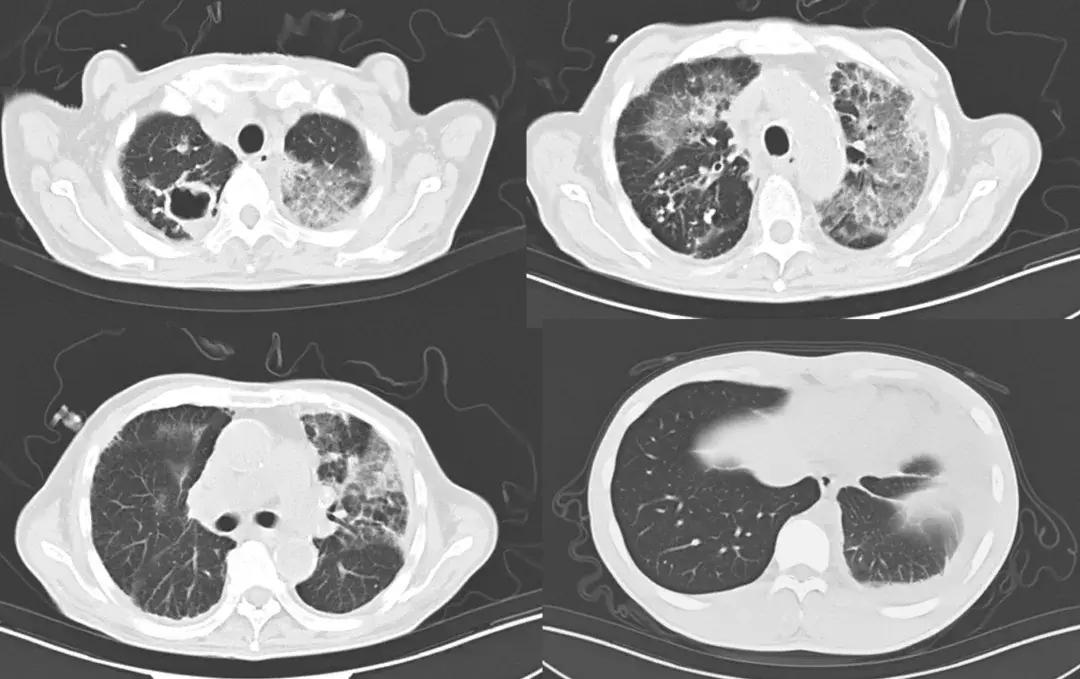

此后患者仍有发热,调整抗生素为比阿培南+利奈咗胺后加强抗感染治疗,体温仍波动在39℃。复查胸部CT(2018-8-20)示:右肺上叶厚壁空洞,两肺上叶及左肺下叶炎性渗出增多,左下少量胸腔积液(图2)。

图2